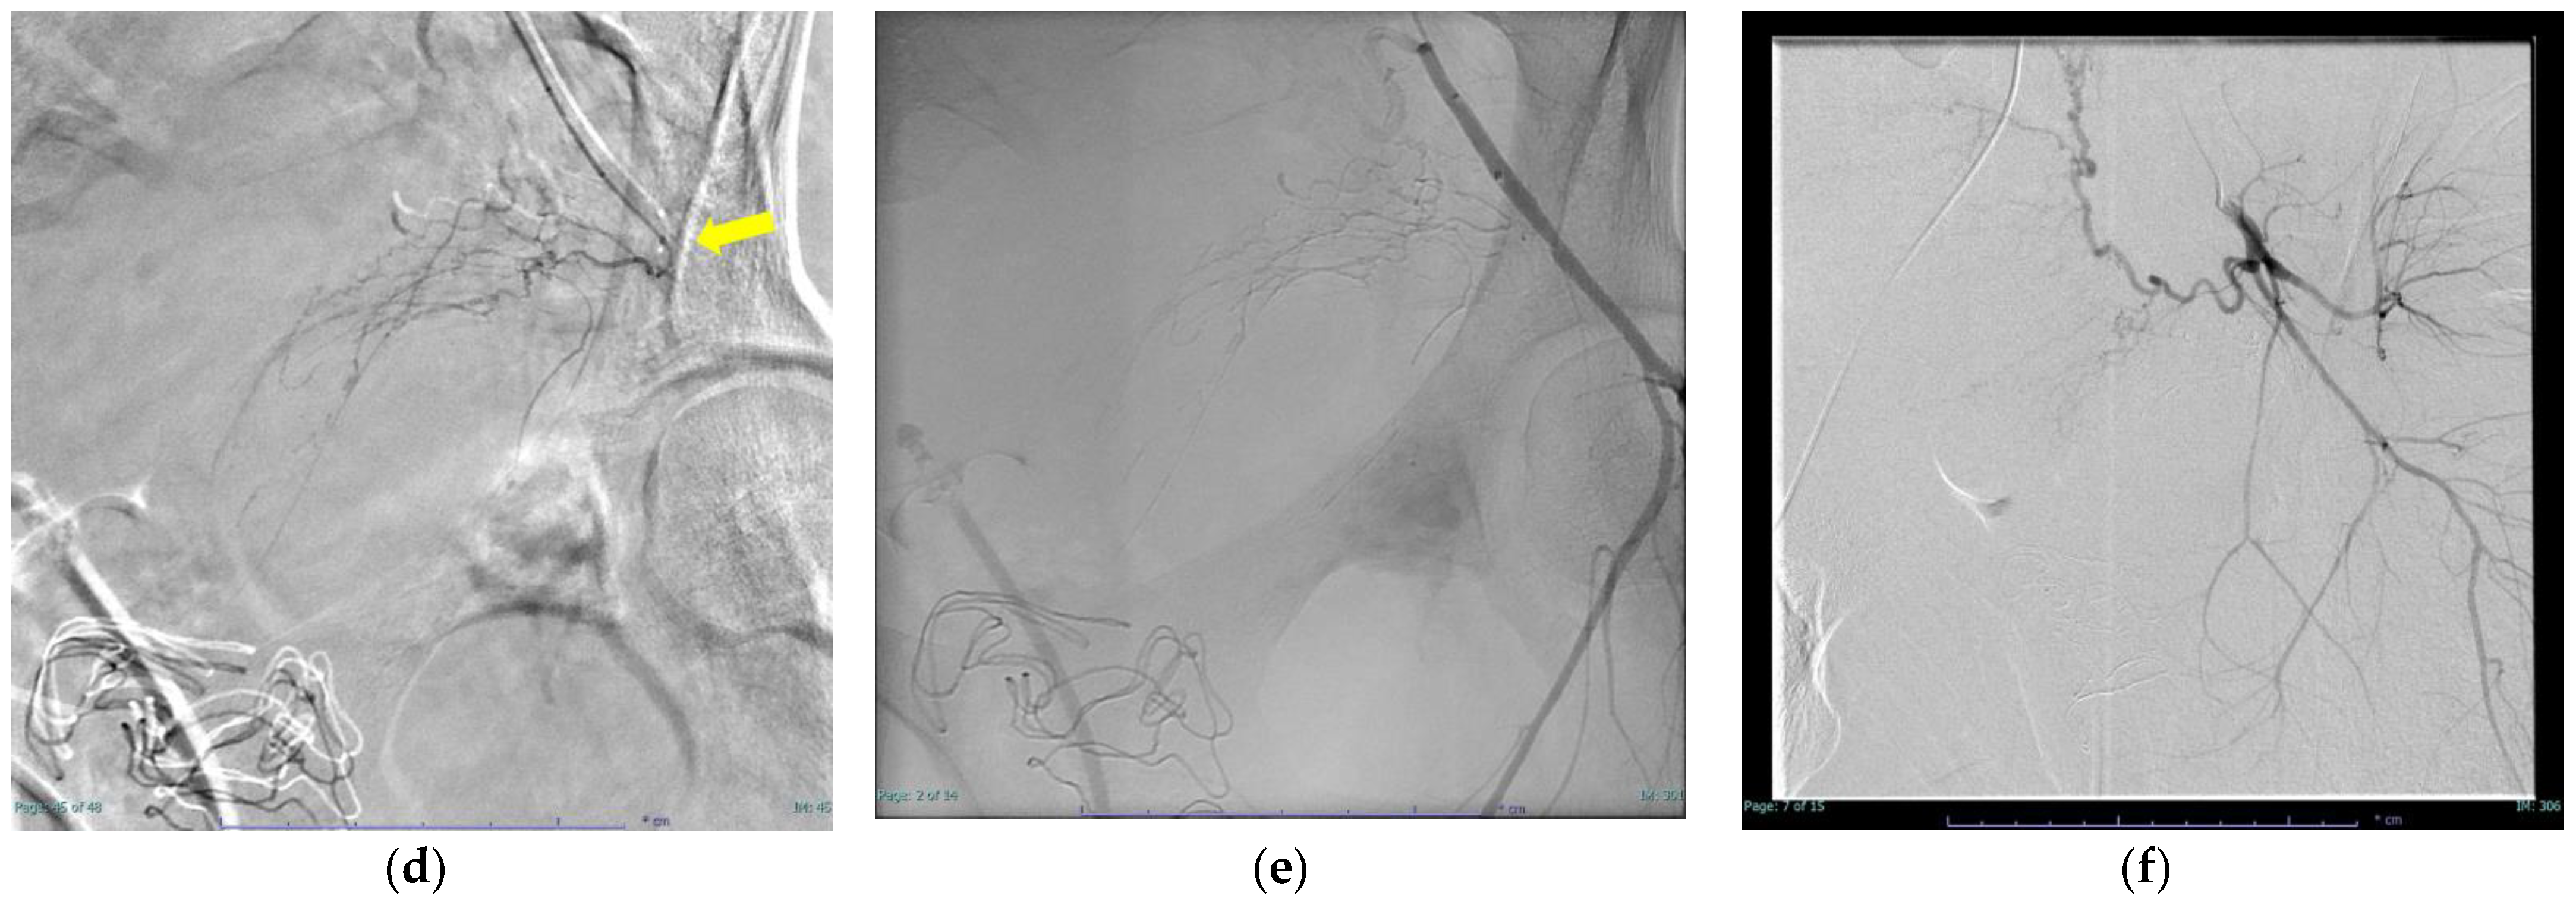

| 5 | 27 | 23.3 | 37/5 | primiparity | normal vaginal delivery | other | 2472 | 2100 | 0.54 | 14.5 | 0.96 | 228 | RBC6U, FFP4U | Hypertensive disorders of pregnancy | operative hemostasis | right internal pudendal artery branch (NBCA:lipodol = 1:4) 0.4 mL |

| 6 | 33 | 21.8 | 40/2 | multiparity | induction of labor | own | 2530 | 12700 | 2.4 | 3 | 2.32 | 37 | RBC36U, FFP30U, PC80U cryoprecipitate12U | Gestational diabetes mellitus Cervical cerclage | ― | left internal pudendal artery branch (NBCA:lipodol = 1:6) 0.3 mL left uterine artery (gelatin sponge) left obturator artery (NBCA:lipodol = 1:4) 0.4 mL |